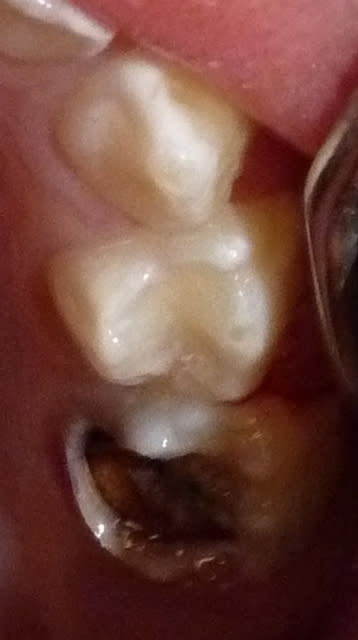

Dans le cas ci-dessous, la 1ère photo est prise après début d’éviction carieuse : sur la 4, on voit déjà la pulpe par transparence. Les tubuli dentinaires d'une dent temporaire sont beaucoup plus larges et nombreux que sur une dent permanente. Ainsi, une carie dentinaire infecte très rapidement la pulpe camérale. Faire une restauration sans pulpotomie dans ce cas aurait probablement abouti à une nécrose à moyen terme.

P1010955 lkrpua - Eugenol

P1010959 qtf3fy - Eugenol

P1010962 ddzmfk - Eugenol

P1010966 tt9pyf - Eugenol

P1010974 bokjpr - Eugenol